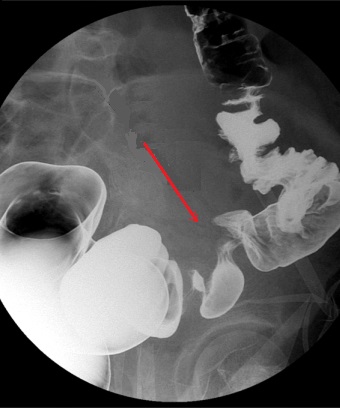

Aspect de stenose excentree

d'une adenocarcinoma du colon sigmoide ( fleche

rouge ) . Lavement

baryte en double de contrast . |

Image stenosant excentrique

( fleche rouge )d'une adenocarcinoma du colon

sigmoide . Sa bord est trres irreguliee , un peu en

diurcissement . Lavement baryte en double de

contrast |